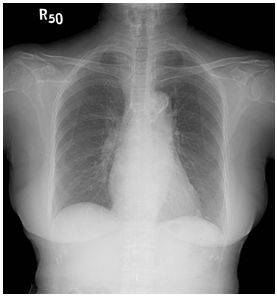

5. 29歲女性,主訴近年來有進展性雙腳水腫,全身倦怠,同時伴有運動性呼吸困難及腹部腫脹。病人在十多年前有紅斑性狼瘡,也因此四處求醫,誤信草藥,終致腎病末期之尿毒,施行血液透析治療。於今年4月24日赴中國接受腎臟移植,不意術後有諸多併發症,如尿路感染等,回國一直在門診治療。近多月來,上述症狀逐漸加劇,乃住院診療。理學檢查:血壓96/55 mmHg;心跳75/min規則;呼吸 18/min,尚屬平穩,病人呈現慢病狀,臉色蒼白,頸靜脈怒張,有Kussmaul's sign,胸部未有濕濁聲,心臟之point of maximal impulse (PMI)不清,S1及S2尚屬正常,未有心雜音,腹部未有肝脾可觸知,雙下肢有水腫。實驗室有WBC,5520;RBC,3,010,000;Hb,10.1 g/dl,BUN,40 mg/dl;Creatinine,1.79mg/dl,餘皆正常。其他胸部X光、心電圖及心臟電腦斷層 如圖示。請問本病人最可能的診斷是: (A) 左心臟衰竭 (B) 右心臟衰竭 (C) 冠心症 (D) 心肌病變 (E) 窄縮性心包膜炎 (constrictive pericarditis)